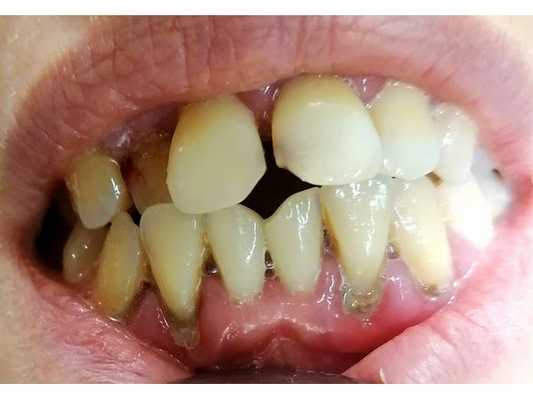

55-летняя женщина обратилась за стоматологической помощью по поводу нынешнего неудовлетворительного состояния ее зубов. Предыдущий стоматолог посоветовал ей провести экстракцию всех безнадежных зубов, но больной при этом было не весьма комфортно осознавать, что ей в дальнейшем все время придется использовать полный съемный протез. В ходе клинического осмотра были обнаружены симптомы умеренного и тяжелого пародонтита, множественные кариозные поражения, а также имеющиеся дефектные реставрации. У пациентки наблюдалось нарушение индивидуальной высоты межчелюстного соотношения, в области отдельных фронтальных зубов прогрессировал феномен Попова-Годона, но, в то же время, передние зубы обеспечивали адекватную поддержку тканям губ (фото 1).

Фото 1. Клинический случай №1: вид зубных рядов с ретрактором.